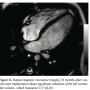

second heart sound. Echocardiogram showed a hugely dilated left ventricle (LV) of unknown cause (LV end-diastolic diameter of 60 mm; z-score, +8). There was mild tricuspid regurgitation with Doppler-derived gradient of 60 mm Hg. Imaging of the branch PAs and the arch was very difficult; hence, the patient was referred for MRI scan to investigate the unusual clinical and echocardiographic findings. Cardiac MRI confirmed severe LV dilation, with end-diastolic volume of 187 mL/m2 (Figure 1) and continuous flow in the left PA throughout systole and diastole, as detected with the phase-contrast flows taken in the left PA (Figure 2). Although the left PA appeared severely stenosed, the stroke volume to both PAs (differential flow) was equal. In addition, the cumulative flow to the PAs was double that of the flow in the main PA, implying that an additional source of flow beyond the PA bifurcation was present. The possibility of an iatrogenic aortopulmonary window was raised and the patient was taken to the catheterization laboratory in order to

His medication was discontinued. His clinical progress was excellent and he started gaining weight. Cardiac MRI 14 months after the percutaneous procedure showed significant reduction of the LV dimensions from 187 to 117 mL/m2 (Figure 6). In addition, the left PA was widely patient and the flow pattern in it had now normalized and was no longer biphasic. The patient remains well and medication free 2 years after the procedure.